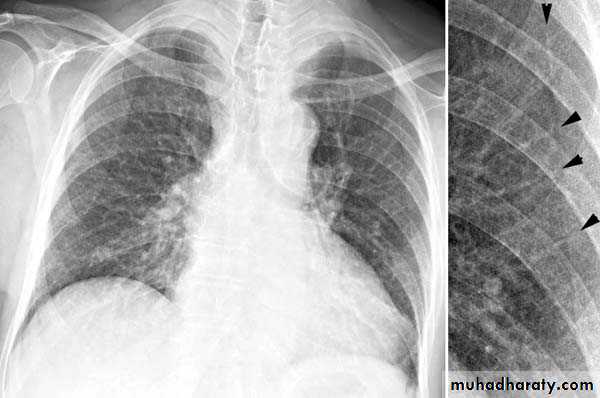

Plain radiographChest radiographs are the most commonly used examination to assess for presence of a pleural effusion, however it should be noted that on a routine erect chest x-ray as much as 250-600 ml of fluid is required before it becomes evident 6. A lateral decubitus film is most sensitive, able to identify even a small amount of fluid. At the other extreme, supine films can mask large quantities of fluid.

A lateral decubitus film (obtained with the patient lying on their side, effusion side down, with a cross table shoot through technique) can visualise small amounts of fluid layering against the dependent parietal pleura.

Both PA and AP erect films are insensitive to small amounts of fluid. Features include:

blunting of the costophrenic angle

blunting of the cardiophrenic angle

fluid within the horizontal or oblique fissures

eventually a meniscus will be seen, on frontal films seen laterally and gently sloping medially (note: